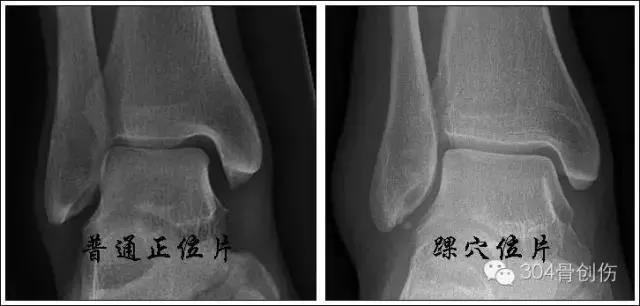

x线检查

下胫腓联合损伤诊断